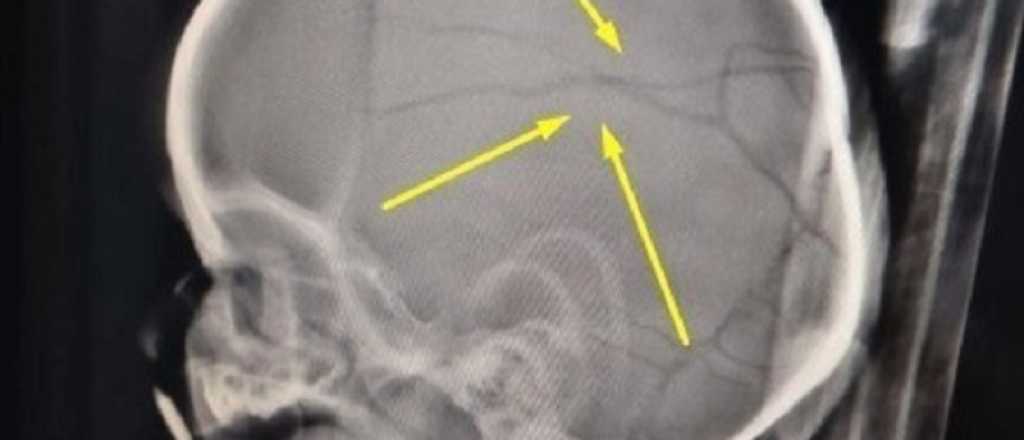

Maximiliano Roth fue condenado por fracturar el cráneo y morder a la hija de su expareja. Un juez lo liberó a cambio de hacer un curso de "deconstrucción de masculinidades" y ahora le fracturó el cráneo a un nene de 11 meses.